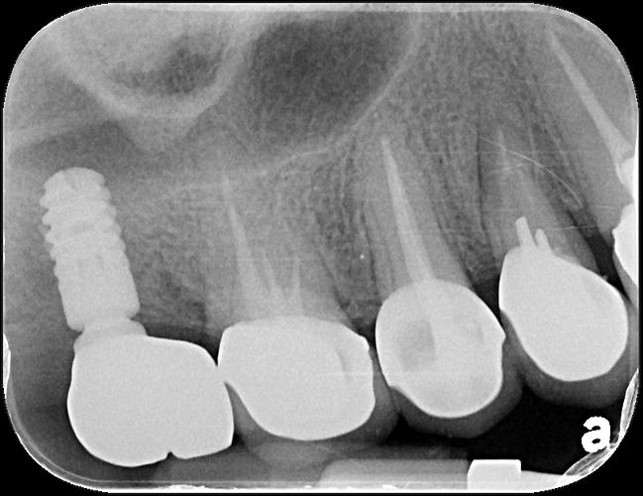

術前、術後比較

治療後,咬合牙周適應良好

治療後,密合度良好